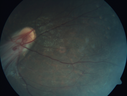

Familial Exudative Vitreoretinopathy - FEVR - Stage 4b OD384 views10 year old child with poor vision OD from birth. The left eye had vascular remodelling in the temporal periphery with preretinal abnormalitlies seen on OCT. The patient never returned for a fluorescein angiogram. Left eye is either stage 1 or stage 2. no family historyJan 01, 2019

Familial Exudative Vitreoretinopathy - FEVR - Stage 4b OD582 views10 year old child with poor vision OD from birth. The left eye had vascular remodelling in the temporal periphery with preretinal abnormalitlies seen on OCT. The patient never returned for a fluorescein angiogram. Left eye is either stage 1 or stage 2. no family historyJan 01, 2019